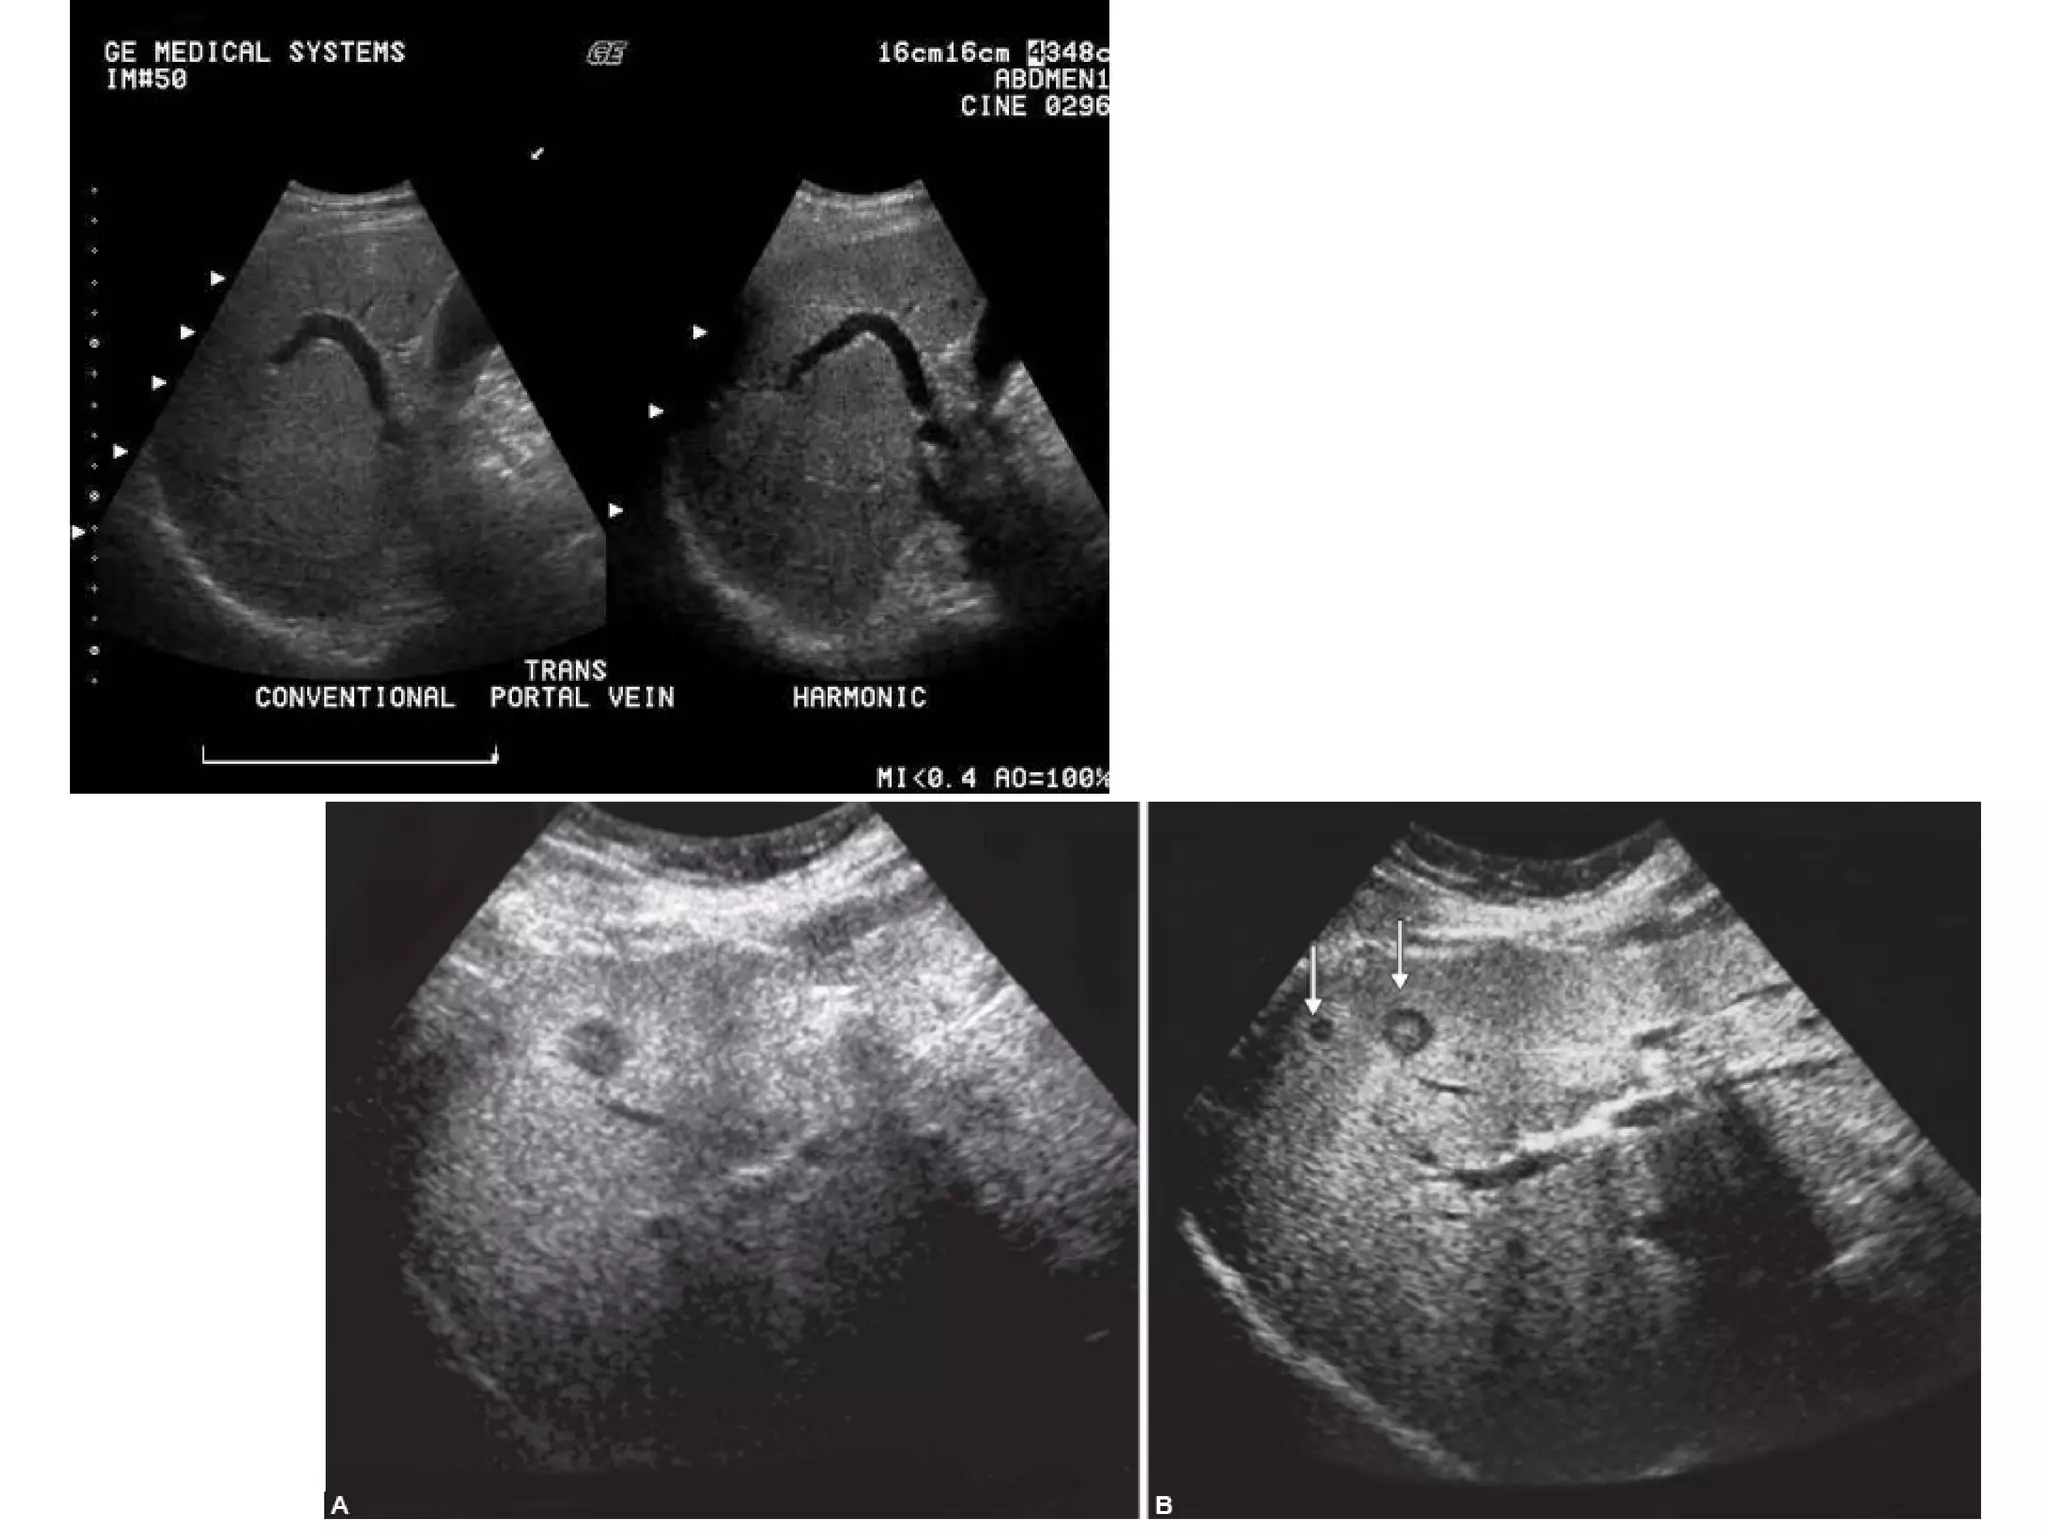

Tissue Harmonic Imaging

Ultrasound beams formed with the harmonic signals have

some interesting properties.

• One of those properties is that the beam formed using the

harmonic signal is narrower and has lower sidelobes.

• The improvement in beamwidth and reduction in side

lobe significantly improves grayscale contrast resolution.

• Furthermore, since the harmonics are generated inside the

body, they only have to pass through the fat layer once (on

receive), not twice (transmit and receive).

• Potential advantages of harmonic imaging

include improved axial resolution due to

higher frequencies and better lateral

resolution due to narrower beams.

• Decreased noise from side lobes improves

signal-to noise ratios and reduces artifacts

• Body fat increases the intensity of harmonic

waves, thus lesion visibility is increased in

obese patients.

• Harmonic imaging increases diagnostic confidence in

differentiating cystic from solid hepatic lesions,

improves detection of gallbladder and biliary calculi,

improves pancreatic definition and allows distinction

of simple from complex renal cysts.